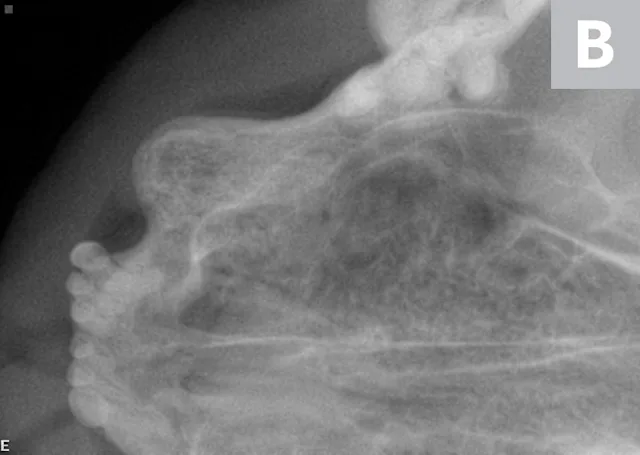

TR is common in cats, occurring in 30% to 60% of all feline patients, and affected cats typically have more than one tooth involved.1-4 In addition, incidence increases with age.1,2,4-6 The mandibular third premolars are the most commonly affected teeth, followed by molars and canines.5,6 TR is progressive, with no known treatment or prevention. Lesions are typically painful, but patients rarely demonstrate outward clinical signs of oral pain.3,7,8

There are 2 main types of TR: type 1 and type 2. Type 1 lesions present with advanced tooth/root resorption but without replacement by bone, whereas type 2 lesions typically present with the lost areas of tooth replaced by bone (ie, replacement resorption). Type 3 TR describes a tooth that has properties of type 1 TR on one root (or area) and type 2 on another.

Etiology

Although numerous theories regarding TR etiology exist, none have been confirmed. TR is known to be caused by odontoclasts (ie, normal cells responsible for remodeling tooth structure). In the normal physiologic process, the resorbed tooth structure is replaced by odontoblasts; however, in TR, these cells are activated and do not downregulate. This, in combination with lack of normal repair, results in tooth destruction.11 Type 1 TR is typically associated with inflammation (eg, caudal stomatitis, periodontal disease).12 In these cases, it is thought that odontoclasts are activated by soft tissue inflammation. Type 2 lesions, in contrast, are generally seen in otherwise healthy mouths; however, the lesions often create local gingivitis. Type 2 TR is a noninflammatory replacement resorption that typically results in ankylosis. The etiology of type 2 TR remains unproven. Lesions start on the root and thus may be seen on dental radiographs prior to oral evidence.

Teeth with type 2 TR have undergone significant replacement resorption. In these cases, the lost root structure is replaced by bone. Therefore, teeth with type 2 TR have a different radiographic density as compared with normal teeth. Radiographic findings typically include areas with no discernible periodontal ligament space (ie, dentoalveolar ankylosis) or root canal. In advanced lesions, there is little to no discernible root structure (ie, ghost roots).